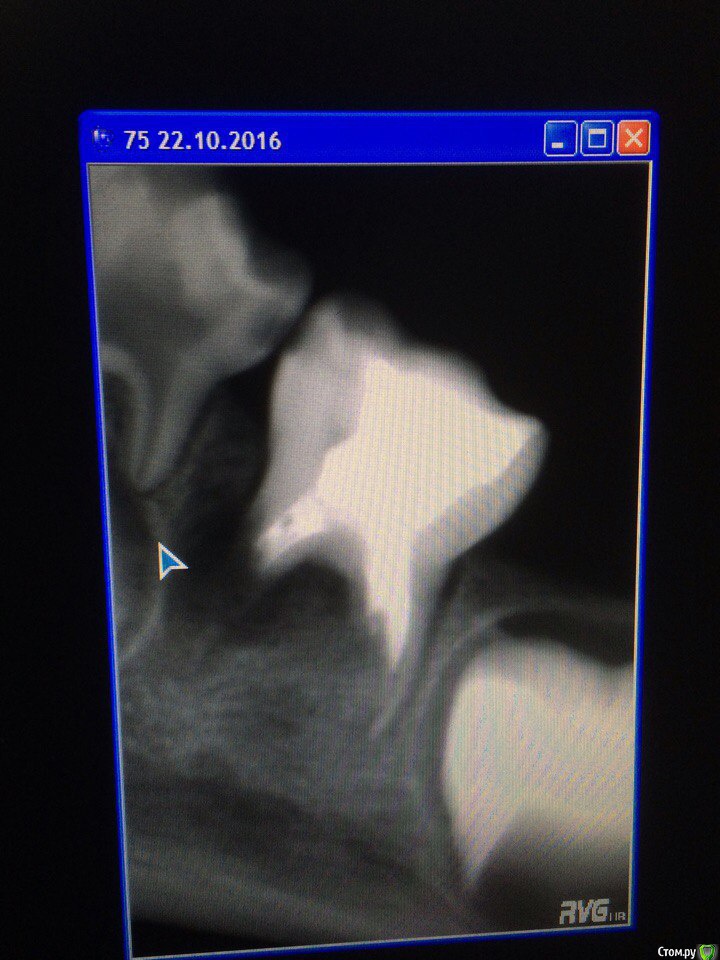

Wrestrus66 Опубликовано 22 октября, 2016 Поделиться Опубликовано 22 октября, 2016 Доброй ночи...Девочки 4 года Пришли ко мне после госки..85 зуб жалобы на ночные боли в итоге анестезию сделать не дела хотел виталку сделать !!В итоге 84,85 безмышьяк.паста...Что скажете по поводу зачатка 85?и что делать с 75зубом ??господа прошу помощи ! Ссылка на комментарий

Stom22 Опубликовано 23 октября, 2016 Поделиться Опубликовано 23 октября, 2016 (изменено) Зачатков ни под 85, ни под 75 на снимке нет. Если 75 не беспокоит, можно оставить, пока сам не выпадет. А так там совсем немного осталось до выпадения, дистальный корень только держит. Зачатка под ним нет. Изменено 23 октября, 2016 пользователем Stom22 Ссылка на комментарий

crown Опубликовано 23 октября, 2016 Поделиться Опубликовано 23 октября, 2016 (изменено) может под 85 он ещё формируется т.к я могу ошибиться возрастом 3-4 года , а чтоб убедиться что нет зачатка 75 нужно сделать снимок симметрично.. У кого ещё какие мысли господа ?!Док я бы убрал 7.5, там воспаление. Огорчает то что была эндодонтия и реставрация герметичная, но увы.. Изменено 23 октября, 2016 пользователем crown Ссылка на комментарий

Stom22 Опубликовано 23 октября, 2016 Поделиться Опубликовано 23 октября, 2016 (изменено) может под 85 он ещё формируется т.к я могу ошибиться возрастом 3-4 года , а чтоб убедиться что нет зачатка 75 нужно сделать снимок симметрично.. У кого ещё какие мысли господа ?!На визиограф делали же снимки? Тут другие зачатки видны, а под 75 его отчётливо нет. Изменено 23 октября, 2016 пользователем Stom22 Ссылка на комментарий

Kota Опубликовано 23 октября, 2016 Поделиться Опубликовано 23 октября, 2016 75 рока оставила бы. только смотреть, что бы воспаление на мезиальном не повредило кортикальную пластинку 34 зуба. потом удалять и держать место. если удалить сейчас, то ребенок начнет жевать на правую сторону. 85 зуб в идеале запломбировать каналы, а если нет, то ампутацию с формокрезолом и цинк эвгенолом, а потом уже в более позднем возрасте попытаться запломбировать каналы. это учитывая то, что метод девитальный. 1 Ссылка на комментарий

Джима Опубликовано 24 октября, 2016 Поделиться Опубликовано 24 октября, 2016 (изменено) так мой снимок постарше, кончик бугра минерализуется уже. у автора, по-моему, тоже видно контуры зачатка.а вот снимок 7.5 выглядит как раз таки так, как будто зачаток был и погиб. Изменено 24 октября, 2016 пользователем Джима Ссылка на комментарий

Stom22 Опубликовано 26 октября, 2016 Поделиться Опубликовано 26 октября, 2016 (изменено) Извиняюсь за дезинформацию. Во внутриутробном периоде, начиная с 5 месяцев, начинается закладка зачатков постоянных зубов и продолжается она до 5 лет. Во внутриутробном периоде закладываются 16 постоянных зубов (все резцы, клыки и первые большие коренные зубы). Все остальные после рождения. Самая поздняя закладка постоянных зубов происходит в 5 лет и это закладка третьего большого коренного зуба. Закладка второго большого коренного зуба происходит в 2,5 года.Ну и зачаток второго малого коренного зуба возникает в 2 года, в 2,5 года оказываются два очага минерализации. Тут же ребёнку 4 года и очагов минерализации мы не видим. Всё таки склоняюсь к тому, что зачатка нет. Но это покажет время. У родителей бы спросила насчёт позднего прорезывания молочных зубов, если имело место такое, то не исключена и поздняя закладка и прорезывание постоянных, но судя по возрасту и снимку всё же остаюсь при своём мнении. Изменено 26 октября, 2016 пользователем Stom22 Ссылка на комментарий

Джима Опубликовано 26 октября, 2016 Поделиться Опубликовано 26 октября, 2016 Stom22. Это зачаток. Время рассудит, конечно, но это зачаток. 99%Искала для вас панорамки, вот нашла: http://pdnr.ru/a4679.html, там есть панорама ребёнка пяти лет. По-моему, на снимке у автора даже минерализацию видно слегка. Переделать бы снимок по-человечески. Ссылка на комментарий